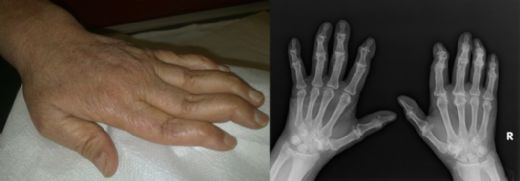

Kas Sinir Hastalıkları: Belirtileri ve Tedavisi Kas sinir hastalıkları, kasların ve sinir sisteminin etkileşimi sonucu ortaya çıkan, genellikle hareket kabiliyetini etkileyen bir dizi durumu kapsamaktadır. Bu hastalıklar, kas zayıflığı, kas atrofisi ve motor sinirlerin hasar görmesi gibi belirtilerle karakterizedir. Bu makalede, kas sinir hastalıklarının belirtileri, nedenleri ve tedavi yöntemleri hakkında ayrıntılı bilgi verilecektir. Kas Sinir Hastalıklarının Belirtileri Kas sinir hastalıkları, bireylerde çeşitli belirtilerle kendini gösterebilir. Bu belirtiler, hastalığın türüne ve ciddiyetine bağlı olarak değişiklik gösterebilir. Genel olarak karşılaşılabilecek belirtiler şunlardır:

Kas Sinir Hastalıklarının Tanısı Kas sinir hastalıklarının tanısı, klinik muayene ve çeşitli testler ile konulur. Tanı sürecinde kullanılan yöntemler şunlardır: